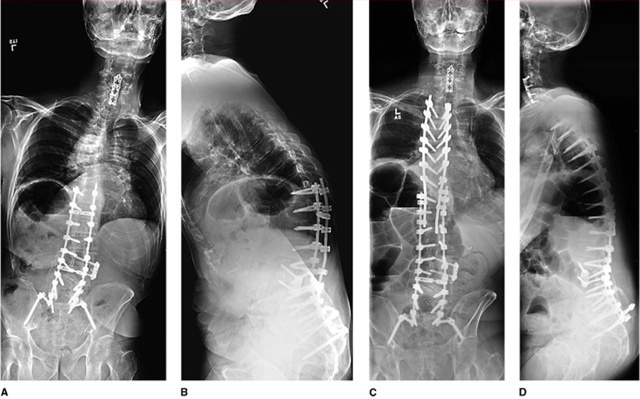

图 1. 74 岁女性,患 parkinson 病和退行性脊柱侧弯。脊柱矫形术后出现 T10 椎体骨折,椎弓根螺钉拔出,近端关节进行性后凸畸形等改变(AB);再次手术治疗,固定至 T3(C、D)